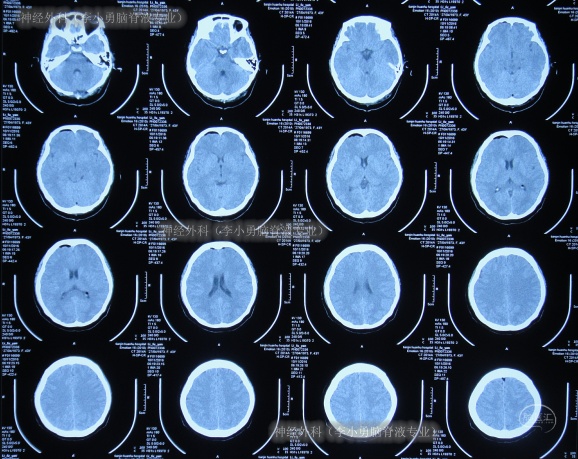

2016年12月15日(后颅窝减压术枕大池成形术37天),再次会诊,查看头颅MRI(图-7)后采用联合抗感染,但体温仍波动在38-38.9℃。

图-7:2016年12月15日头颅MRI

联合抗感染4天即2016年12月18日,查头颅MRI(图-8)后继续联合抗感染。

图-8:2016年12月18日头颅MRI

2016年12月27日(腰大池引流术后5天),第3次会诊后继续使用联合抗感染治疗7天至2017年1月2日,查MRI(图-9):小脑扁桃体下疝后颅窝减压术后改变;双侧上颌窦及蝶窦、右额窦黏膜增厚。治疗期间脑脊液培养血培养均无细菌生长。

图-9:2017年1月2日头颅MRI

停药后6天即2017年1月9日,患者病情仍无好转,于是转院至北京的李小勇脑脊液专业。